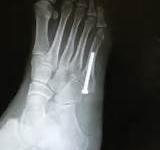

第五跖骨骨折如何治疗?

第一:跖骨骨折是一种常见的骨折,多因重物打击足背、辗压,足内翻扭伤或误踢硬物而引起,临床表现主要为脚部疼痛,肿胀,畸形。但不同部位的跖骨骨折表现也略有不同,分为第五跖骨基部撕脱骨折和行军骨折。

第三:跖骨骨折会留有后遗症,一般包括骨折本身造成的不可避免的后遗症如骨缺血坏死,骨骺损伤所致骨发育障碍等,目前尤其尚无方法预防,其他后遗症如骨折不愈合,畸形愈合,关节功能障碍等是可以预防的。